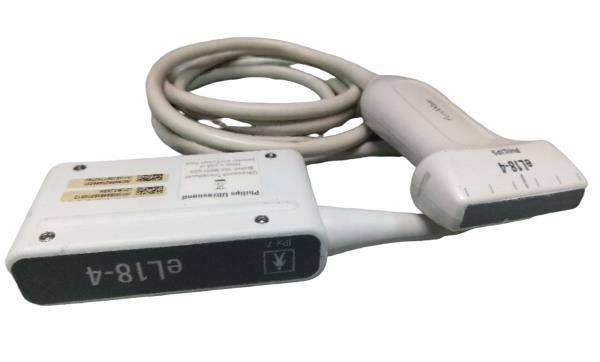

The Laptop Ultrasound Scanner is designed to provide clear and precise imaging, making it an essential tool for healthcare professionals. This device offers advanced functionality, allowing doctors to perform a wide range of examinations. Because it includes a transvaginal probe, it is particularly effective for gynecological assessments, ensuring accurate diagnosis.